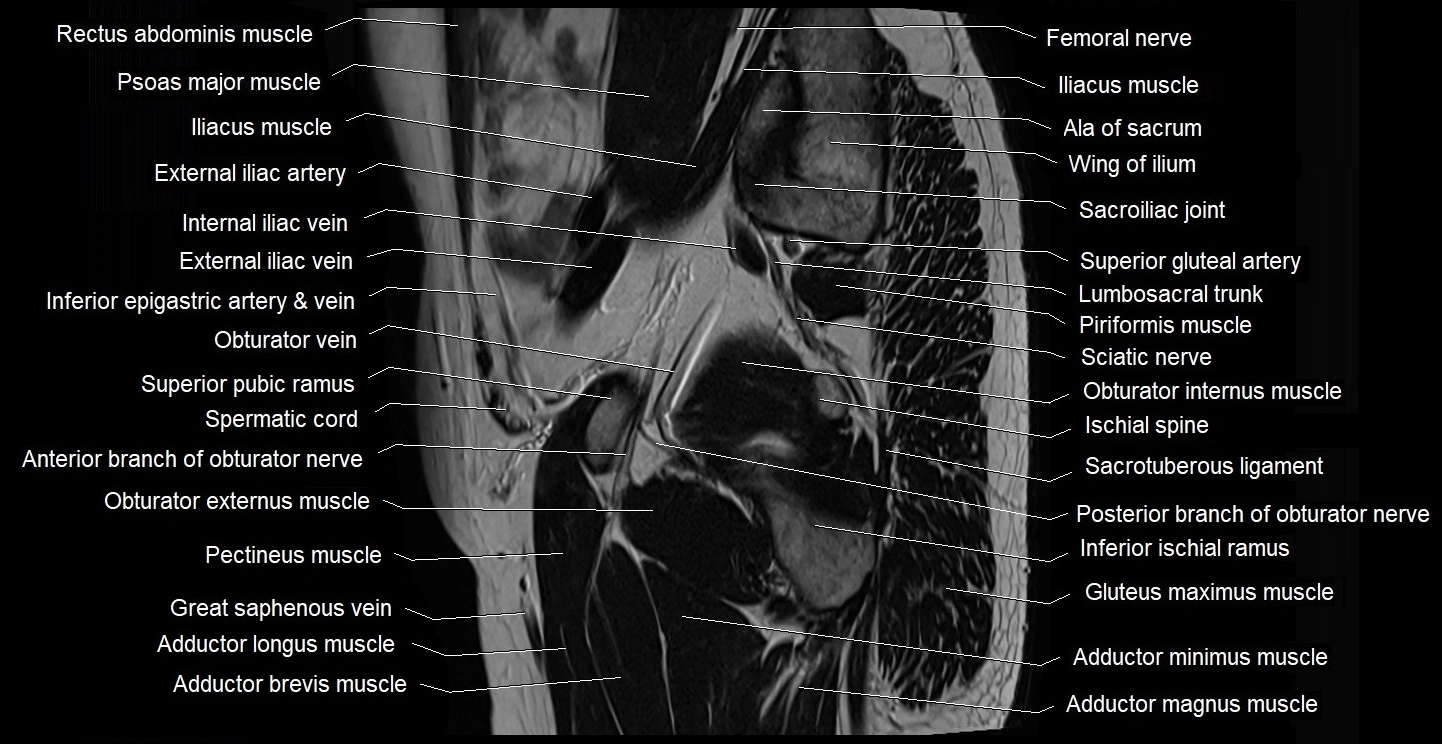

- Adductor brevis muscle

- Adductor longus muscle

- Adductor magnus muscle

- Adductor minimus muscle

- Ala of sacrum

- External iliac artery

- External iliac vein

- Femoral nerve

- Femoral vein

- Gluteus maximus muscle

- Gluteus medius muscle

- Gluteus minimus muscle

- Gracilis muscle

- Iliopsoas muscle

- Iliopsoas tendon

- Inferior epigastric artery

- Inferior epigastric veins

- Inferior pubic ramus

- Internal iliac vein

- Internal oblique muscle

- Ischial spine

- Ischiofemoral ligament

- Lumbosacral trunk

- Obturator externus muscle

- Obturator internus muscle

- Obturator nerve

- Obturator vein

- Pectineus muscle

- Piriformis muscle

- Posterior division of obturator nerve (Posterior branch of obturator nerve)

- Psoas major muscle

- Pubic bone

- Sacral plexus

- Sacroiliac joint

- Sacrospinous ligament

- Sacrotuberous ligament

- Sartorius muscle

- Sciatic nerve

- Spermatic cord

- Superior gluteal artery

- Superior pubic ramus

- great saphenous vein